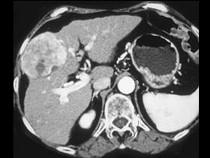

问题 女,55岁,右上腹痛,消瘦乏力3个月,请结合图像诊断为()

选项 A.肝血管瘤 B.肝腺瘤 C.肝癌 D.肝脓肿 E.肝转移癌

答案 C